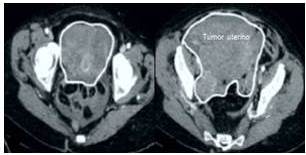

La ecografía abdomino-pélvica reveló que la tumoración medía 20 cm x 13 cm x 9 cm encontrándose una lesión en cara posterior que medía 6 cm x 4 cm x 3 cm que se extendía hacia el fondo de saco de Douglas. Los anexos estaban desplazados hacia delante con pequeña cantidad de líquido libre en cavidad abdominal. El hígado bazo y páncreas estaban normales. No se observaron evidencias de carcinomatosis y ambos anexos estaban normales. La ecografía Doppler confirmó la naturaleza hiper-vascular del tumor. Las imágenes de tomografía computada demostraron la presencia del tumor de origen pélvico, que desplazaba asas intestinales (Figura 1). No se encontró ascitis, carcinomatosis y adenopatías retroperitoneales. Los valores de los marcadores tumorales fueron CA125: 91,5 UI/mL, alfafetoproteína: 315 ng/mL, y deshidrogenasa láctica 1 059 UI/mL. Los valores de gonadotropina coriónica y antígeno carcino-embriogénico estaban dentro de límites normales. Tanto la endoscopia superior como la colonoscopia no mostraron alteraciones. La radiografía simple de tórax estaba normal.